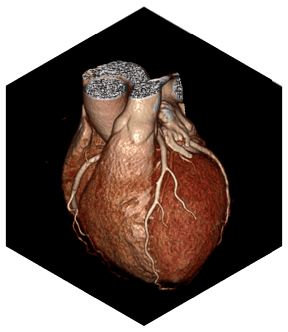

- Интеллектуальная платформа коронарной визуализации мгновенно замораживает сердце и отображает информацию высокого разрешения о сердечно-сосудистых структурах, стентах, кальцификации и бляшках с помощью уникальной интеллектуальной системы управления и алгоритмов коронарной реваскуляризации SinoVision.

- Расширенный коронарный анализ

- Определяет степень стеноза и состав бляшки коронарной артерии, помогает при послеоперационном осмотре при шунтировании и стентировании